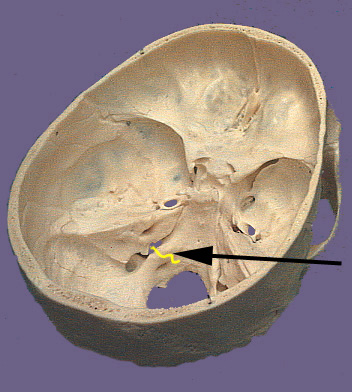

Cranium CN X

The vagus nerve is the longest of the cranial nerve. Its name is derived from Latin meaning "wandering". True to its name the vagus nerve wanders from the brain stem through organs in the neck, thorax and abdomen. The nerve exits the brain stem through rootlets in the medulla that are caudal to the rootlets for the ninth cranial nerve. The rootlets form the tenth cranial nerve and exit the cranium via the jugular foramen. Similar to the ninth cranial nerve there are two sensory ganglia associated with the vagus nerve. They are the superior and inferior vagal ganglia. The branchial motor component of the vagus nerve originates in the medulla in the nucleus ambiguus. The nucleus ambiguus contributes to the vagus nerve as three major branches which leave the nerve distal to the jugular foramen. The pharyngeal branch travels between the internal and external carotid arteries and enters the pharynx at the upper border of the middle constrictor muscle. It supplies the all the muscles of the pharynx and soft palate except the stylopharyngeas and tensor palati. These include the three constrictor muscles, levator veli palatini, salpingopharyngeus, palatopharyngeus and palatoglossal muscles. The superior laryngeal nerve branches distal to the pharyngeal branch and descends lateral to the pharynx. It divides into an internal and external branch. The internal branch is purely sensory and will be discussed later. The external branch travel to the cricothyroid muscle which it supplies. The third branch is the recurrent branch of the vagus nerve and it travels a different path on the left and right sides of the body. On the right side the recurrent branch leave the vagus anterior to the subclavian artery and wraps back around the artery to ascend posterior to it. The right recurrent branch ascends to a groove between the trachea and esophagus. The left recurrent branch leaves the vagus nerve on the aortic arch and loops posterior to the arch to ascend through the superior mediastinum. The left recurrent branch ascends along a groove between the esophagus and trachea. Both recurrent branches enter the larynx below the inferior constrictor and supply intrinsic muscles of larynx excluding the cricothyroid. The visceromotor or parasympathetic component of the vagus nerve originates from the dorsal motor nucleus of the vagus in the dorsal medulla. These cells give rise to axons that travel in the vagus nerve. The visceromotor part of the vagus innervates ganglionic neurons which are located in or adjacent to each target organ. The target organs in the head-neck include glands of the pharynx and larynx (via the pharyngeal and internal branches). In the thorax branches go to the lungs for bronchoconstriction, the esophagus for peristalsis and the heart for slowing of heart rate. In the abdomen branches enter the stomach, pancreas, small intestine, large intestine and colon for secretion and constriction of smooth muscle. The viscerosensory component of the vagus are derived from nerves that have receptors in the abdominal viscera, esophagus, heart and aortic arch, lungs, bronchia and trachea. Nerves in the abdomen and thorax join the left and right vagus nerves to ascend beside the left and right common carotid arteries. Sensation from the mucous membranes of the epiglottis, base of the tongue, aryepiglottic folds and the upper larynx travel via the internal laryngeal nerve. Sensation below the vocal folds of the larynx is carried by the recurrent laryngeal nerves. The cell bodies that give rise to the peripheral processes of the visceral sensory nerves of the vagus are located in the inferior vagal ganglion. The central process exits the ganglion and enters the brain stem to terminate in the nucleus solitarius. The general sensory components of the tenth cranial nerve conduct sensation from the larynx, pharynx, skin the external ear and external auditory canal, external surface of the tympanic membrane, and the meninges of the posterior cranial fossa. Sensation from the larynx travels via the recurrent laryngeal and internal branches of the vagus to reach the inferior vagal ganglion. Sensory nerve fibers from the skin and tympanic membrane travel with auricular branch of the vagus to reach the superior vagal ganglion. The central processes from both ganglia enter the medulla and terminate in the nucleus of the spinal trigeminal tract.